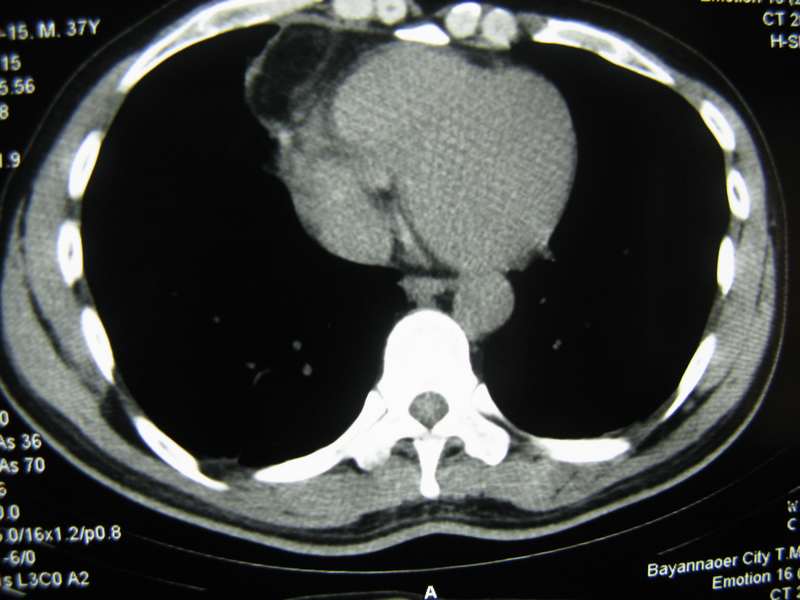

男,37岁,主述胸疼厉害,无咳嗽,无发热,血象也不高,病灶内ct值脂肪密度,右侧胸腔内少量积液,同道们考虑什么?谢谢!

两肺下叶基底段纤维灶,右肺下叶基底背侧相应胸膜肥厚,右肺中叶内侧段部分不张。前中下纵隔团块状脂肪影,随访除外胸腺脂肪瘤。

不除外膈疝。